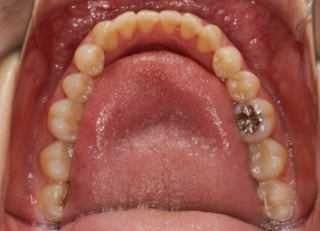

治療前

治療後(2年4ヶ月後)

骨格的左右非対称+オープンバイト反対咬合

治療法:フルパッシブブラケット:T21+タングトレーニング

解説:顔面の骨格的な左右非対称とオープンバイト反対咬合、舌突出癖が認められる、非常に難しい症例です。